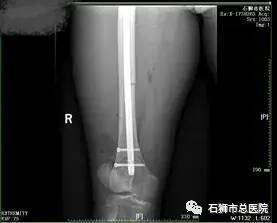

股骨骨折

股骨粗隆间粉碎性骨折

在学科建设提升技术方面,骨科这两年没有停止步伐。近年来,骨科对常见四肢骨折均能熟练进行接骨板或髓内针内固定术;对关节内骨折的诊断和治疗具有丰富的临床经验,尤其在促使老年骨折患者减少卧床时间、促进骨折愈合减少并发症发生取得良好临床效果。这些成绩,在陆陆续续健康出院的患者、及他们送来的感谢信中得到验证。